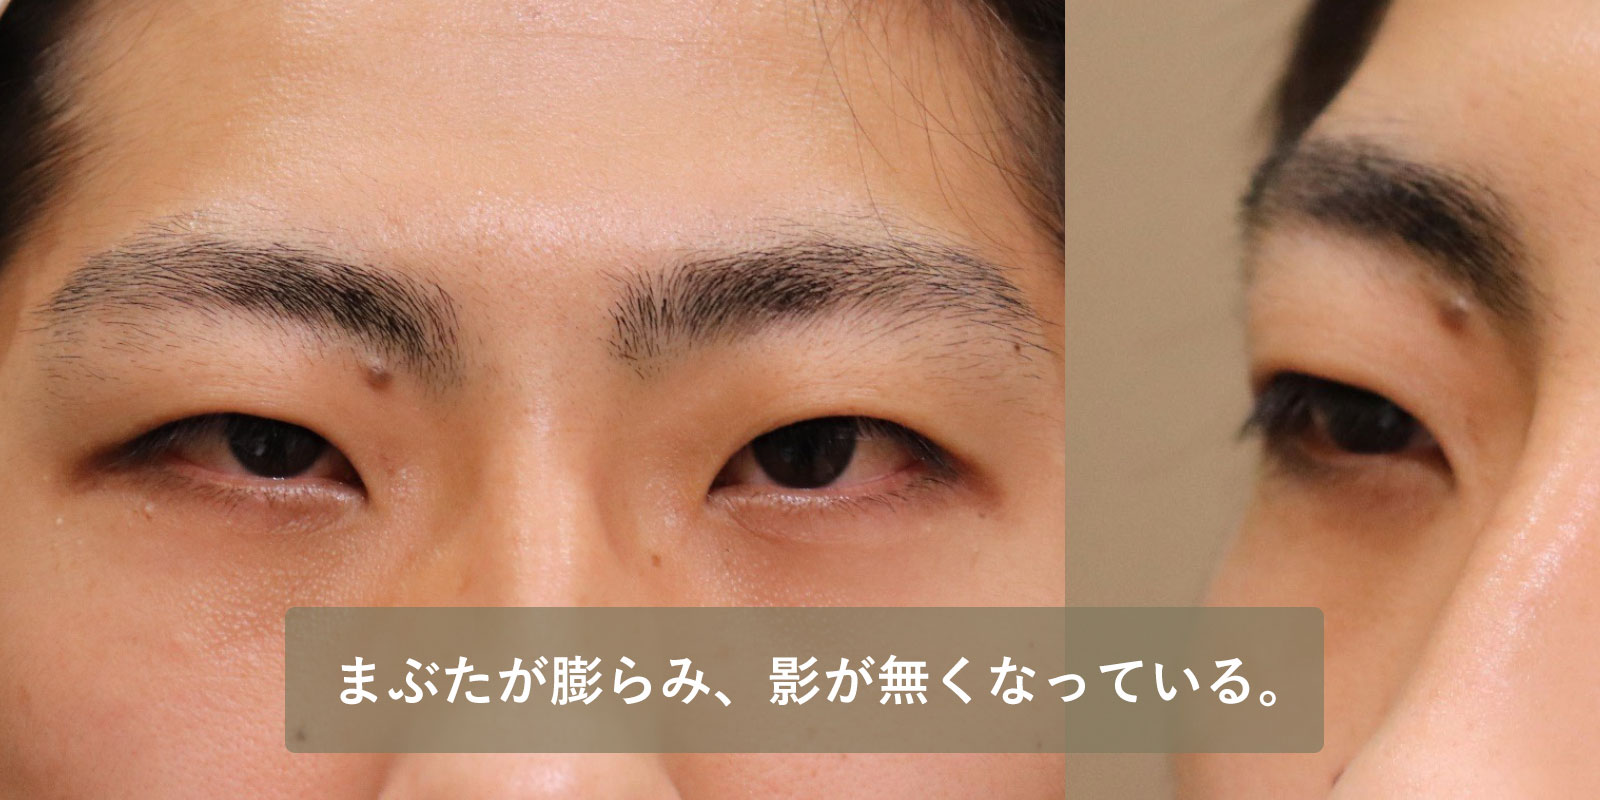

| 術前 | 眼球陥凹があり、わずかだが上眼瞼に影が出来ており、眉毛よりまぶたが凹んでいる。 |

|---|---|

| 術後 | まぶたが膨らみ、影が無くなり、眉毛よりまぶたが突出している。 |